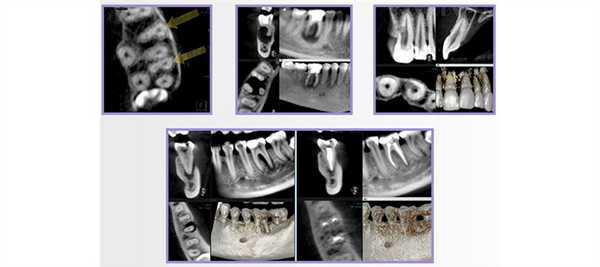

Качество пломбирования 4.7 зуба, по данным КЛКТ, было неудовлетворительным. В мезиально-щечном и дистальных каналах 4.7 зуба пломбировочный материал прослеживался в виде отдельных фрагментов (рис. 3) . Мезиально-язычный канал обтурирован неплотно, до апикальной стриктуры (рис. 4). Наблюдали признаки апикальной резорбции дистального корня (рис. 5) .

Рис. 3. КЛКТ, косо-сагиттальная и корональная томограммы мезиального корня 4.7 зуба. Выведен мезиально-щечный канал 4.7 зуба.

Рис. 4. КЛКТ, косо-сагиттальная и корональная томограммы мезиального корня 4.7 зуба. Выведен мезиально-язычный канал 4.7 зуба.

Рис. 5. КЛКТ, косо-сагиттальная и корональная томограммы дистального корня 4.7 зуба.

В периапикальной области обоих корней определялся обширный сливной очаг деструкции кости протяженностью 11х6 мм, который распространялся до кортикальной выстилки нижней челюсти канала с ее локальным разрушением (рис. 6) .

Рис. 6. КЛКТ, МПР. Прицельная визуализация апикальных очагов деструкции в обл. 4.7 зуба.

Параллельно с этим на КТ была выявлена несостоятельность реставрации 4.6 зуба. Пациентке было рекомендовано провести его лечение. Однако она обратилась в клинику только через полгода с острой болью в области 4.6 зуба. После клинического обследования и анализа особенностей строения канально-корневой системы 4.6 зуба на КЛКТ (рис. 7) было проведено эндодонтическое лечение 5-канального нижнего правого первого моляра по поводу необратимого симптоматического периодонтита 4.6 зуба.

Рис. 7. КЛКТ, МПР. Прицельная визуализация дистального корня 4.6 зуба.